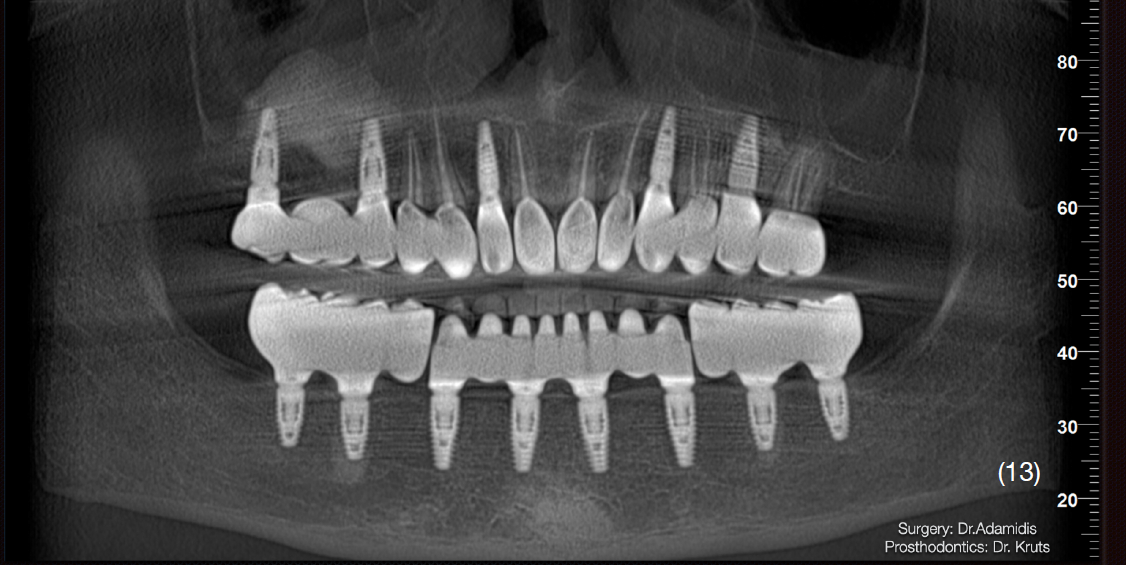

Етап 1. Робота з нижньою щелепою:

Екстракція наявних зубів та одномоментне встановлення 8 імплантатів Straumann BLT з використанням навігаційного хірургічного шаблону. В це ж відвідування було зафіксовано тимчасову конструкцію з рівня імплантатів, без використання мультиюніт-абатментів. Станом на цей момент для тимчасової реабілітації верхньої щелепи вже було виготовлено та зафіксовано провізорну конструкцію з опорою на зуби.

Одномоментно з кістковою аугментацією встановлено імплантати Strauman BLT діаметром 3.3mm в ділянках 12, 15, 17, 23, 25 зубів. Операційну рану було ушито, зворотньо зафіксовано тимчасову конструкцію на наявних зубах.

На нижню щелепу було виготовлено роздільну конструкцію. В бічних ділянках – мостоподібні протези на гвинтовій фіксації з рівня імплантату.

У фронтальній ділянці комбінована конструкція – каркас із діоксиду цирконію, фіксований до імплантатів гвинтами, на який цементуються коронки із прес-кераміки. Такий тип конструкції вибрано через високу надійність та прогнозованість в довготривалій перспективі, що підтверджується даними клінічних досліджень, а також легкість в обслуговуванні.

Верхню щелепу реабілітовано коронками з опорою на зуби та імплантати.